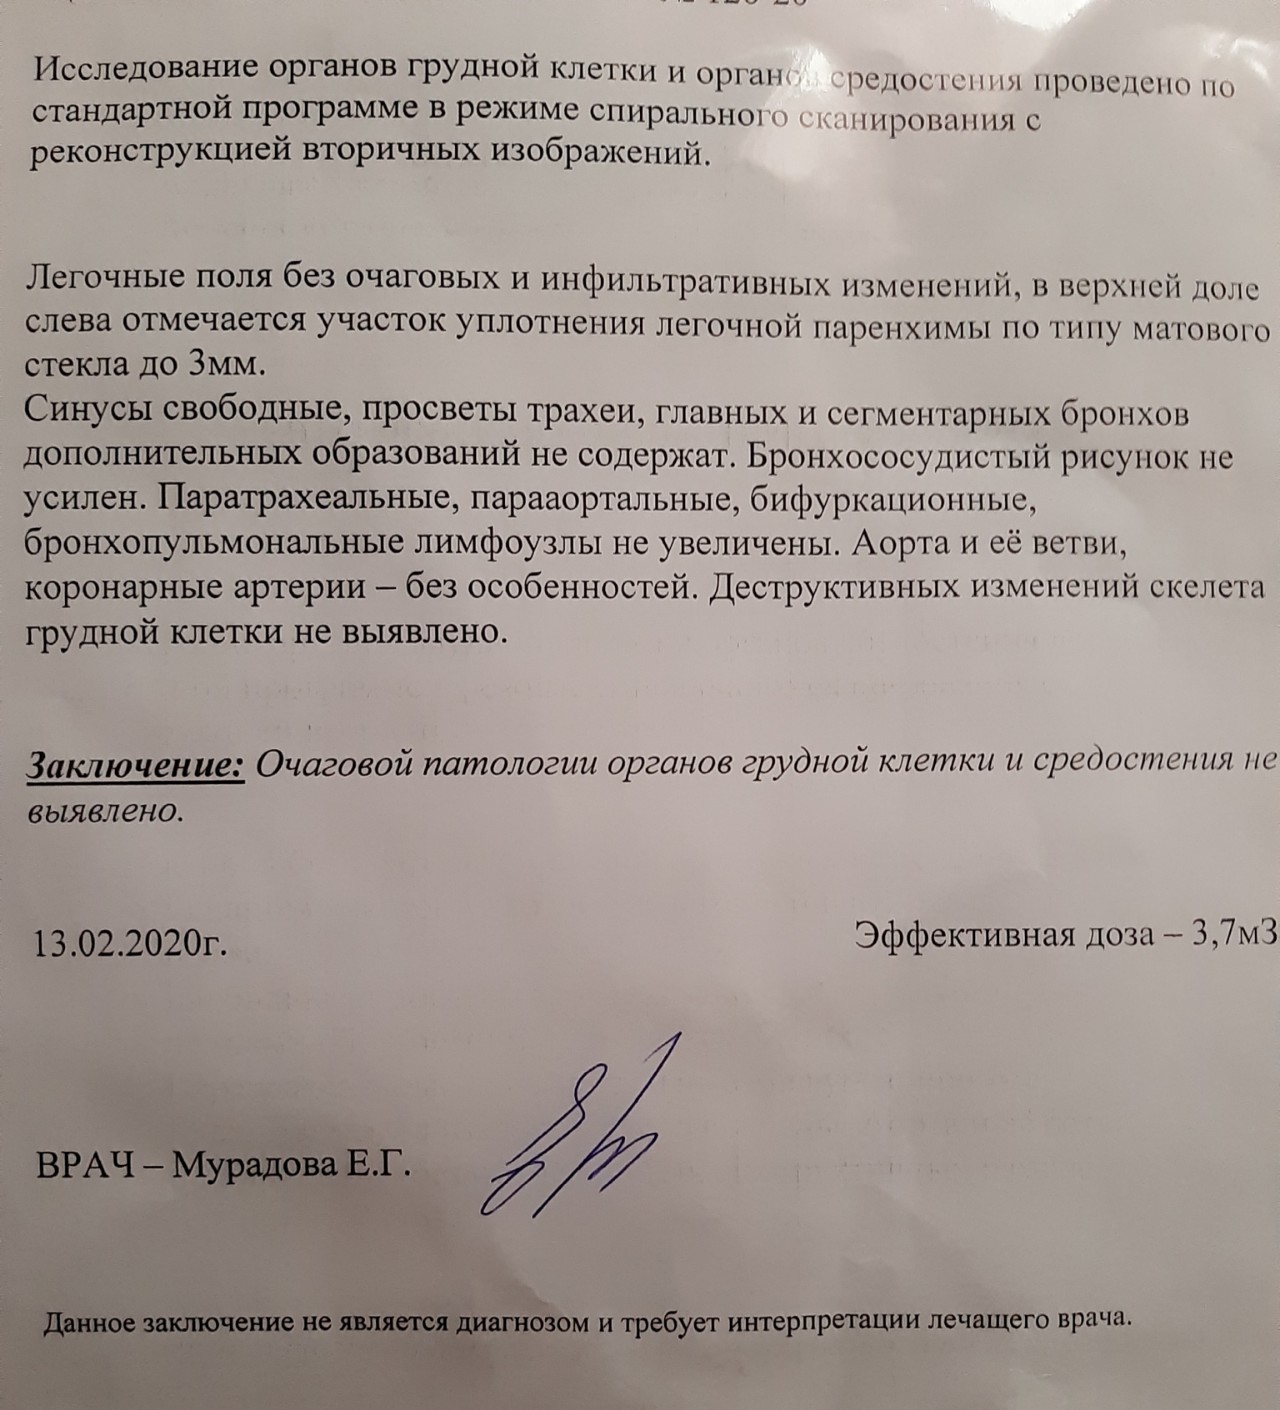

Фотографии и снимки КТ легких без контрастных веществ

Раздел: Визуальный дайджест